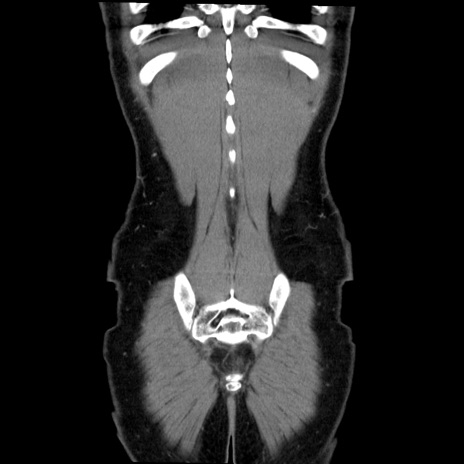

症例36(冠状断像)

【症例】20歳代 男性

【主訴】心窩部痛

【現病歴】今朝より上腹部痛あり。一旦軽快していたが再度出現したため救急要請。昨日夕に白身の魚を含む刺身を食べた。

【身体所見】BP 136/89mmHg、HR 74/min、BT 37.0℃、腹部:膨満、軟、心窩部に圧痛あり。反跳痛なし、筋性防御なし、腸雑音やや亢進あり。

【データ】WBC 17700、CRP 0.48